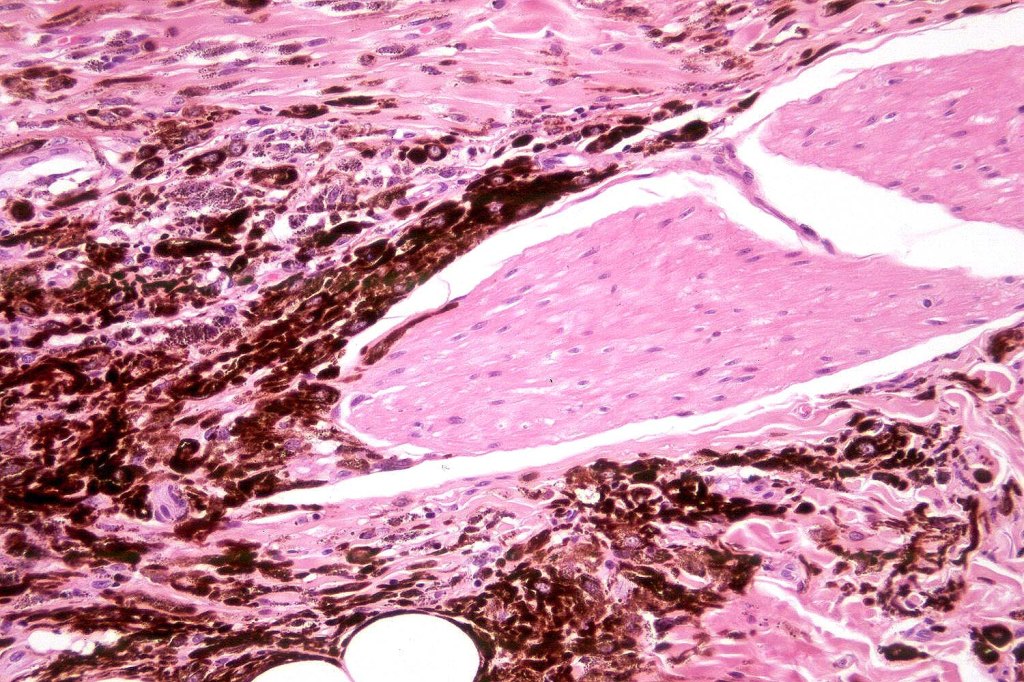

Histological features

•Most characteristic is the dumbbell silhouette although a plague morphology may also be encountered

•Admixture of spindle cells, pigmented bipolar or dendritic cells & melanophages

•An alveolar pattern is characteristic particularly with clear cell nodules

•Stromal fibrosis, myxoid change, vascular hyalinization with cyst formation are often seen